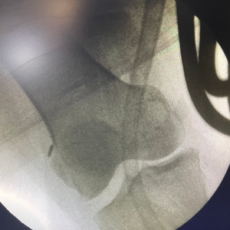

The Bikini Incision Hip Replacement is a minimally invasive surgery that involves making a small, cosmetically favorable incision along the bikini line. This approach significantly reduces tissue damage, minimizes scarring, and accelerates recovery times, allowing patients to return to their daily activities more swiftly.